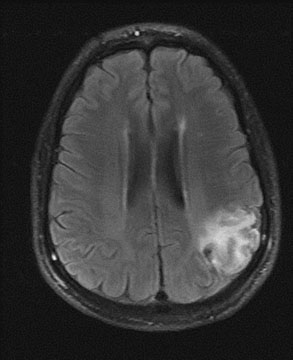

As diffusion-perfusion MRI and other techniques to quantify blood flow, such as perfusion CT and xenon-CT, become more widely available, clinicians will be better equipped to estimate the relative benefits and risks of thrombolysis, based more on physiologic data than rigid time constraints. Patients with large areas of penumbra tissue would benefit most, while those with large tissue volume with blood flow under 10 mL per 100 g/min would not benefit and may be at increased risk for hemorrhage. A recent report utilizing diffusion-perfusion MRI to guide thrombolysis with desmoteplase allowed the safe and apparently efficacious administration of this thrombolytic agent up to 9 hours after the onset of ischemia.45 Figure 1 exemplifies the use of diffusion-perfusion MRI in acute stroke treatment. Ideally, multimodal testing of the parenchyma to exclude hemorrhage, a viability study to determine the amount of salvageable brain, and a vascular study to assess vessel patency would provide the clinician with the information to make rational decisions regarding the need to treat. Magnetic resonance (MRI, diffusion-perfusion imaging, and magnetic resonance angiography [MRA]) and CT technology (with CT perfusion and CT angiography) have the potential to guide this multimodal evaluation.

Fig. 1. An 81-year-old man with atrial fibrillation developed acute onset of left-sided weakness and presented to hospital 3 hours and 40 minutes after onset of symptoms. A: The diffusion-sequence magnetic resonance imaging (MRI), with infracted tissue in the right basal ganglia in white. B: Decreased perfusion in the right middle cerebral artery distribution (white area). Given the relatively small diffusion abnormality and the large perfusion defect, it was decided to proceed with thrombolysis despite the time elapsed.